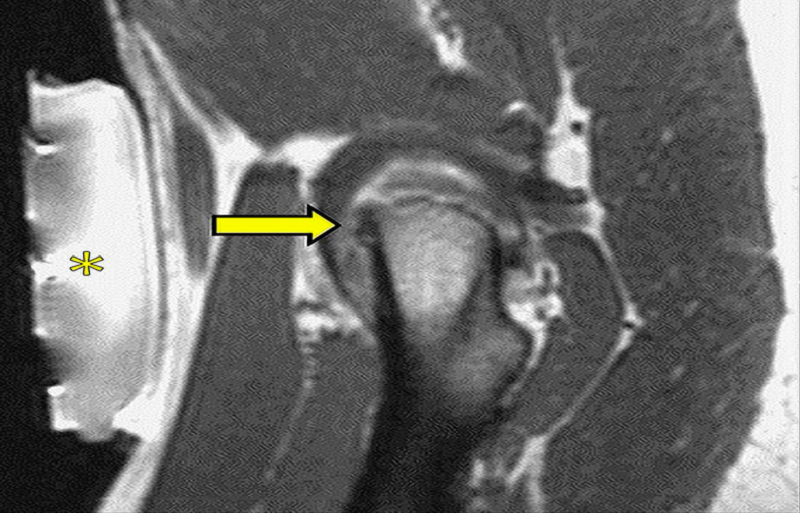

圖:磁共振引導下的復發(fā)性軟組織腫瘤冷凍消融

另一個優(yōu)點是可以連續(xù)(即使是雙傾角,典型的超聲制導),加上熱控制,評估燒蝕區(qū)域。

消融的圖像引導通常由MRI表示,為正確的光束瞄準和溫度映射提供解剖信息。